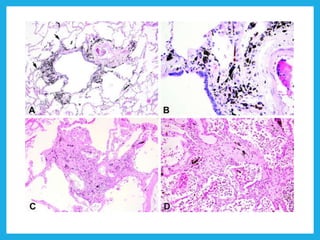

• #8 A, Grade 1 asbestosis consists of fibrosis involving the bronchiolar wall and extending to the first layer of alveoli (arrows). B, Higher magnification shows asbestos bodies embedded within the fibrous tissue. C, Grade 2 asbestosis consists of fibrosis involving more distant alveolar walls but which spares at least some alveoli between adjacent bronchioles. D, Grade 3 asbestosis consists of fibrosis involving all alveoli between 2 adjacent bronchioles (hematoxylin-eosin, original magnifications ×60 [A and C], ×300 [B], ×125 [D]).